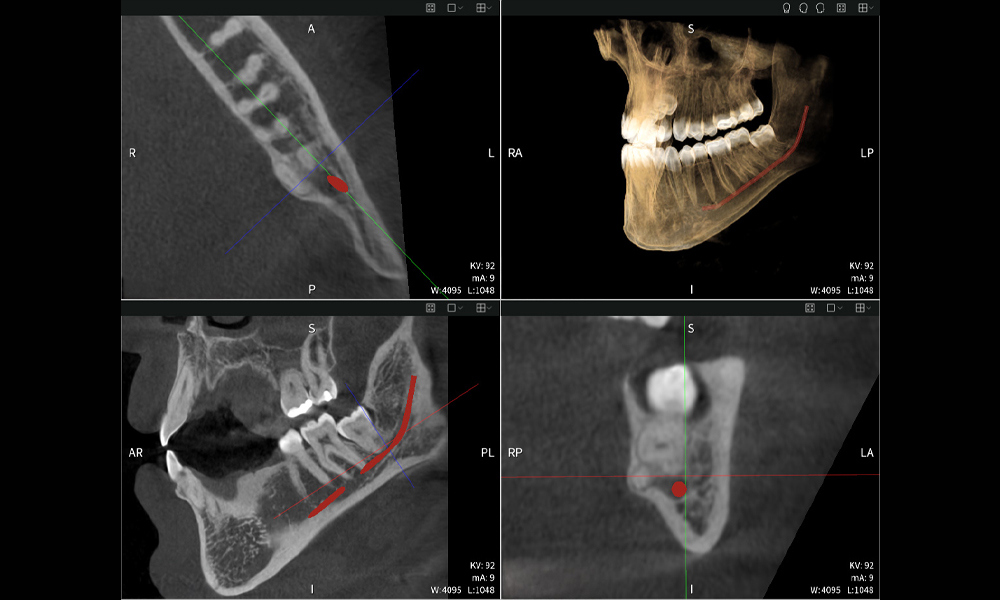

Figures b–d show various views of a 3D reconstruction of the mandible, providing a comprehensive overview of the mandibular anatomy, the position of the nerves in relation to the teeth, and allowing assessment of tooth symmetry and alignment.

Figure d shows the previously treated tooth 48, with its crown removed, and its roots left in proximity to the nerve, illustrating the high risk of nerve damage.